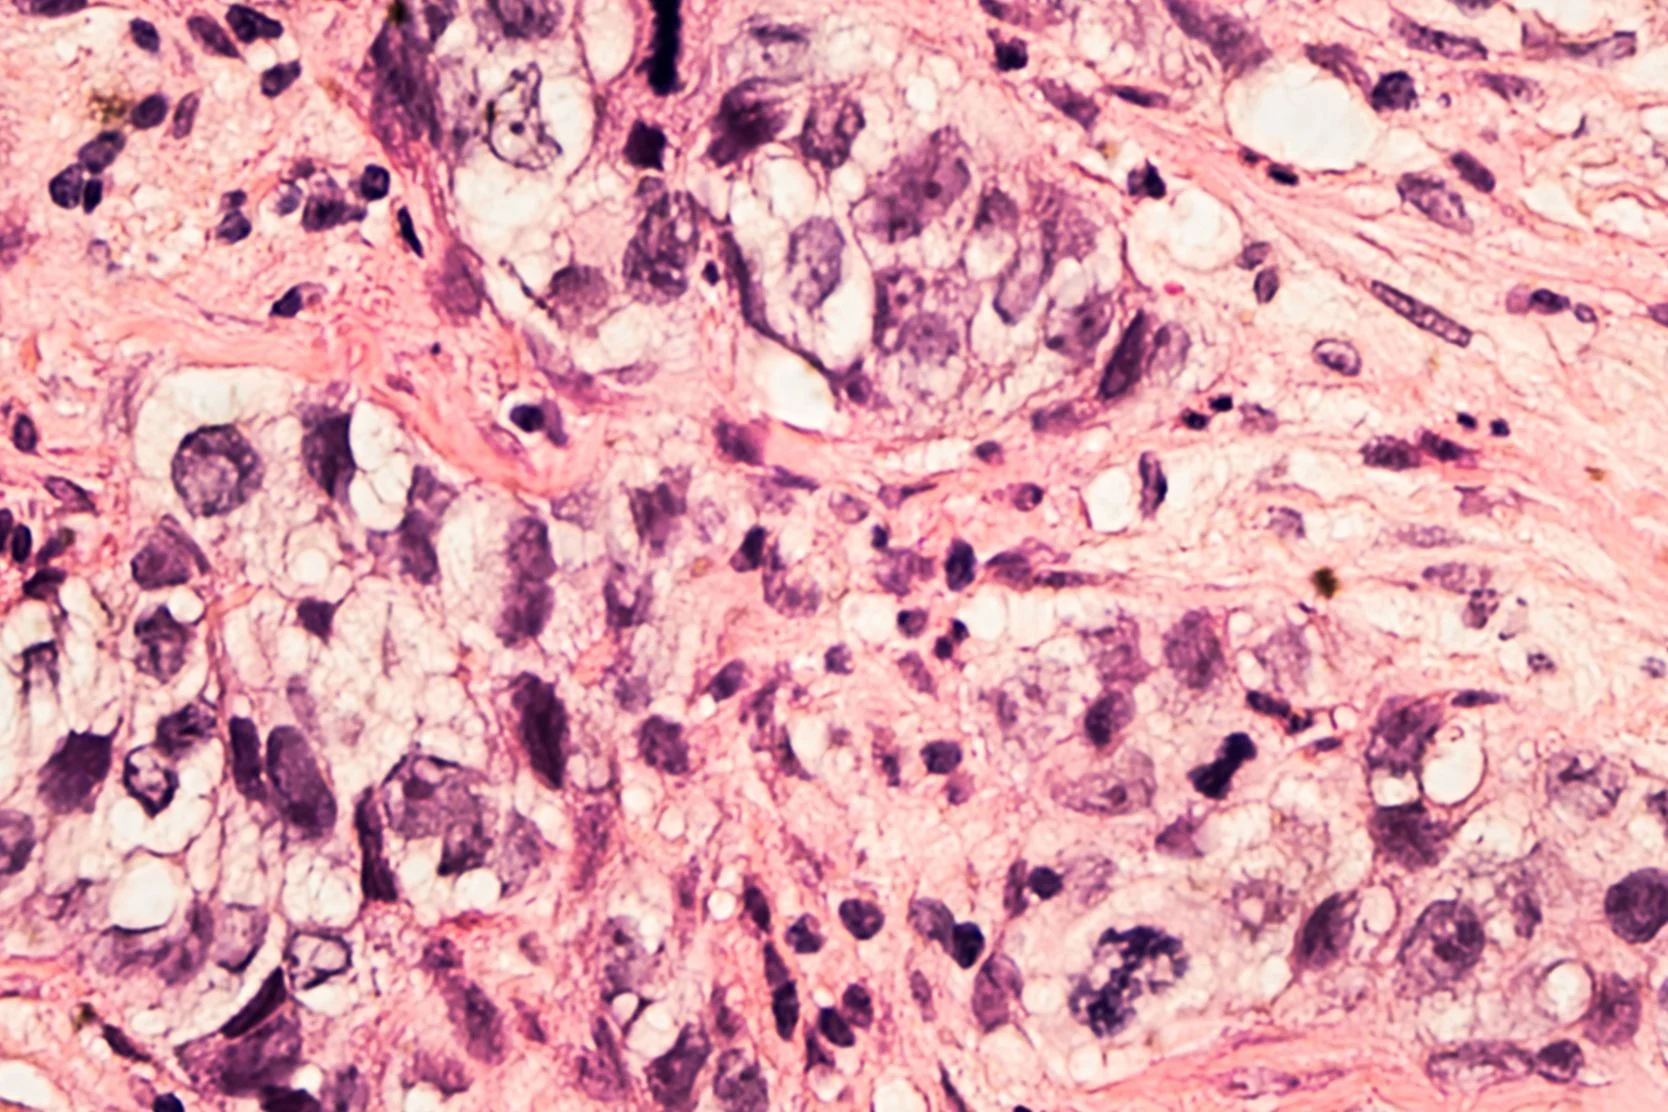

A biopsy may be used to determine whether a breast lump or other abnormal tissue is cancer. During a biopsy, a surgeon, pathologist or radiologist removes a portion or all of the suspicious tissue. The tissue is then examined under a microscope by a pathologist, who checks for cancer cells and makes the diagnosis.